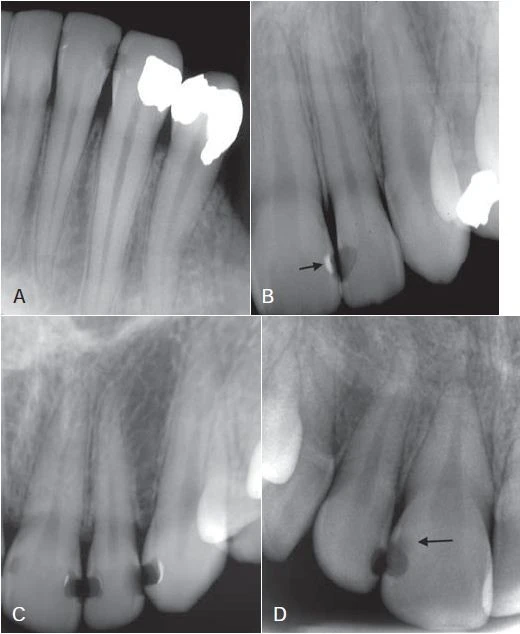

Hình 2. Hình ảnh X quang của tổn thương sâu răng không hoạt động (vùng đen), một nửa xuyên qua men răng vẫn còn nguyên vẹn, với bề mặt được khoáng hoá (mũi tên)

Hình 3. Phim cánh cắn phần hàm trái của bệnh nhân.

Hình 4. Phim cánh cắn ở bộ răng hỗn hợp cho thấy tổn thương sâu ngà ở mặt gần và xa răng cối sữa thứ hai và tổn thương men ở mặt gần răng cối lớn vĩnh viễn thứ nhất. Tổn thương lan rộng ở thân và chân răng cối sữa thứ nhất hàm dưới.

Hình 6. Phim cánh cánh thể hiện sâu răng mặt bên (mũi tên)

Hình 7. Sâu răng lan rộng vào phần ngà răng

Hình 10. Những hình ảnh dương tính giả (mũi tên)